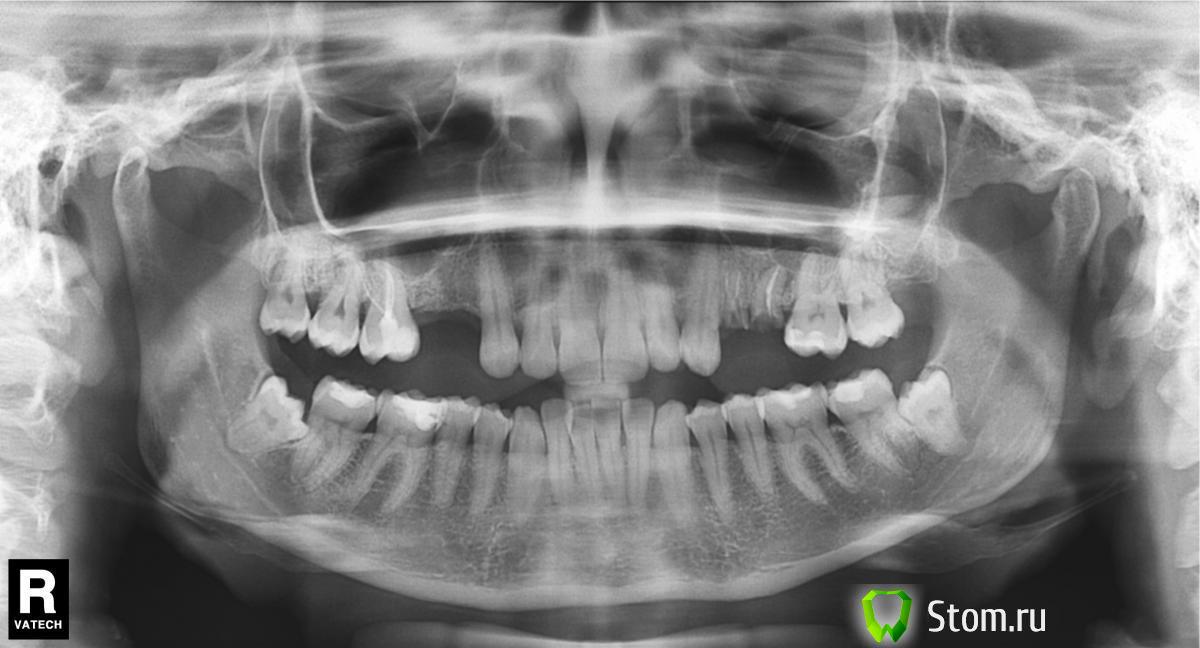

Merk Опубликовано 30 марта, 2012 Поделиться Опубликовано 30 марта, 2012 Уважаемые доктора! Нужен совет! Снимок внизу. Мой врач предлагает сделать сразу удаление корней 4,5 слева, синус лифтинг с обоих сторон, удаление двух нижних восьмерок, установку 4-х имплантов вверху слева и справа. Импланты корейские implantium или superline. Через 3-4 мес. установка формирователей, потом коронки.Вопрос1 Можно ли делать все сразу (анестезия предлагается - седация) или лучше поэтапно?2 Есть вариант лечиться у доктора, который работает с Nobel. Какая система лучше? Какая дороже?3 При синуслифтинге предлагается закладывать аллоплант (если я что-то не так называю поправьте) в составе которого какая-то фракция моей крови, костный материал крупного рогатого скота, стружка моей кости, синтетический материал. Насколько этот состав оптимален, другой доктор использует только синтетический материал. Что лучше?4 На 5 зубе слева киста и постоянно надувается над зубом мешочек с гноем. Врач сказал что все это вычистит, как это может повлиять на приживление?5 И последний вопрос,извините за объем, в данной клинике выполняются операции с одномоментной установкой коронок наимплант, т.е. сразу все под ключ. Не подозрительно ли это?Заранее спасибо за советы Ссылка на комментарий

Dr. Surkin Опубликовано 30 марта, 2012 Поделиться Опубликовано 30 марта, 2012 Уважаемые доктора! Нужен совет! Снимок внизу. Мой врач предлагает сделать сразу удаление корней 4,5 слева, синус лифтинг с обоих сторон, удаление двух нижних восьмерок, установку 4-х имплантов вверху слева и справа. Импланты корейские implantium или superline. Через 3-4 мес. установка формирователей, потом коронки.Вопрос1 Можно ли делать все сразу (анестезия предлагается - седация) или лучше поэтапно?2 Есть вариант лечиться у доктора, который работает с Nobel. Какая система лучше? Какая дороже?3 При синуслифтинге предлагается закладывать аллоплант (если я что-то не так называю поправьте) в составе которого какая-то фракция моей крови, костный материал крупного рогатого скота, стружка моей кости, синтетический материал. Насколько этот состав оптимален, другой доктор использует только синтетический материал. Что лучше?4 На 5 зубе слева киста и постоянно надувается над зубом мешочек с гноем. Врач сказал что все это вычистит, как это может повлиять на приживление?5 И последний вопрос,извините за объем, в данной клинике выполняются операции с одномоментной установкой коронок наимплант, т.е. сразу все под ключ. Не подозрительно ли это?Заранее спасибо за советы В таких случаях обязательно необходимо изучать местные анатомические условия с помощью компьютерной томографии.В пазухах есть костные шипы/перегородки, что резко усложняет операцию синус-лифта.Нужно хорошо знать соотношение корней 6-х верхних зубов с дном пазухи, чтобы при синус-лифте, при отслойке слизистой оболочки, не повредить сосудисто-нервные пучки, входящие в корни. Наличие инфицированного зуба с активным свищевым ходом ставит под вопрос поведение подсаженного костного материала и имплантата. Удаление 25 зуба возможно будет сопровождаться перфорацией слизистой оболочки гайморовой пазухи. В связи с этим рекомендую сначала удалить 4 и 5 слева, подождать 3-4 месяца, затем сделать Конусно-лучевую компьютерную томограмму и только после делать все манипуляции. Вид костного материала (своя кость, костный материал животных или кораллов и т.д.) для синус-лифта в принципе не играет большой роли, учитывая имеющийся у Вас объем кости по высоте. Проведение 2-х синус-лифтов и удаление 2-х нижних 8-к в принципе выполнимо, но, конечно, не особо приятно. Одномоментно установить ВРЕМЕННЫЕ коронки на имплантаты сразу после синус-лифтов и имплантации - слишком рискованно. Ссылка на комментарий